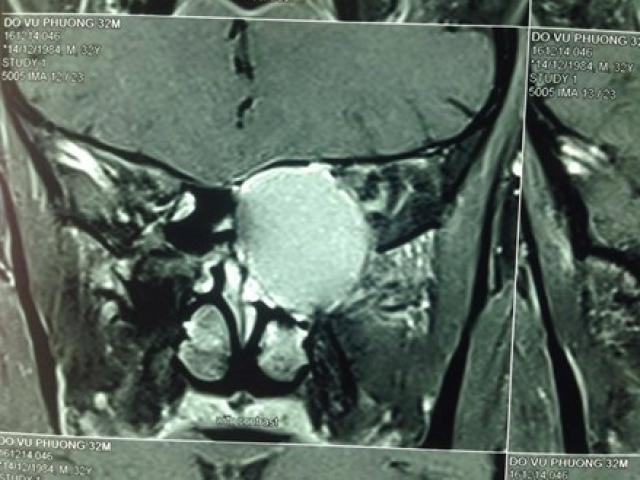

Chiều ngày 20/12, TS Phạm Văn Bình- Trưởng Khoa Ngoại Tổng hợp Tân Triều (Bệnh viện K) cho biết, bệnh nhân Nguyễn Văn Yết, 84 tuổi ở Mỹ Lộc, Nam Định đến bệnh viện K khám với khối u cứng như đá to như người mang bầu 9 tháng với mong ước duy nhất bác sĩ giúp cắt bỏ khối u.

Ca mổ kéo dài gần 5 tiếng, khối u nặng khoảng 10 kg được lấy ra. Với khối u có đường kính lớn (45 cm), các phẫu thuật phải phẫu tích rất tỉ mỉ, vừa mổ vừa cầm máu. Khối u được cắt toàn bộ, bảo toàn thận và niệu quản bên trái,kiểm soát mạch máu lớn xâm lấn. Bệnh nhân được truyền 12 đơn vị máu, gần bằng lượng máu của cơ thể một người trưởng thành.